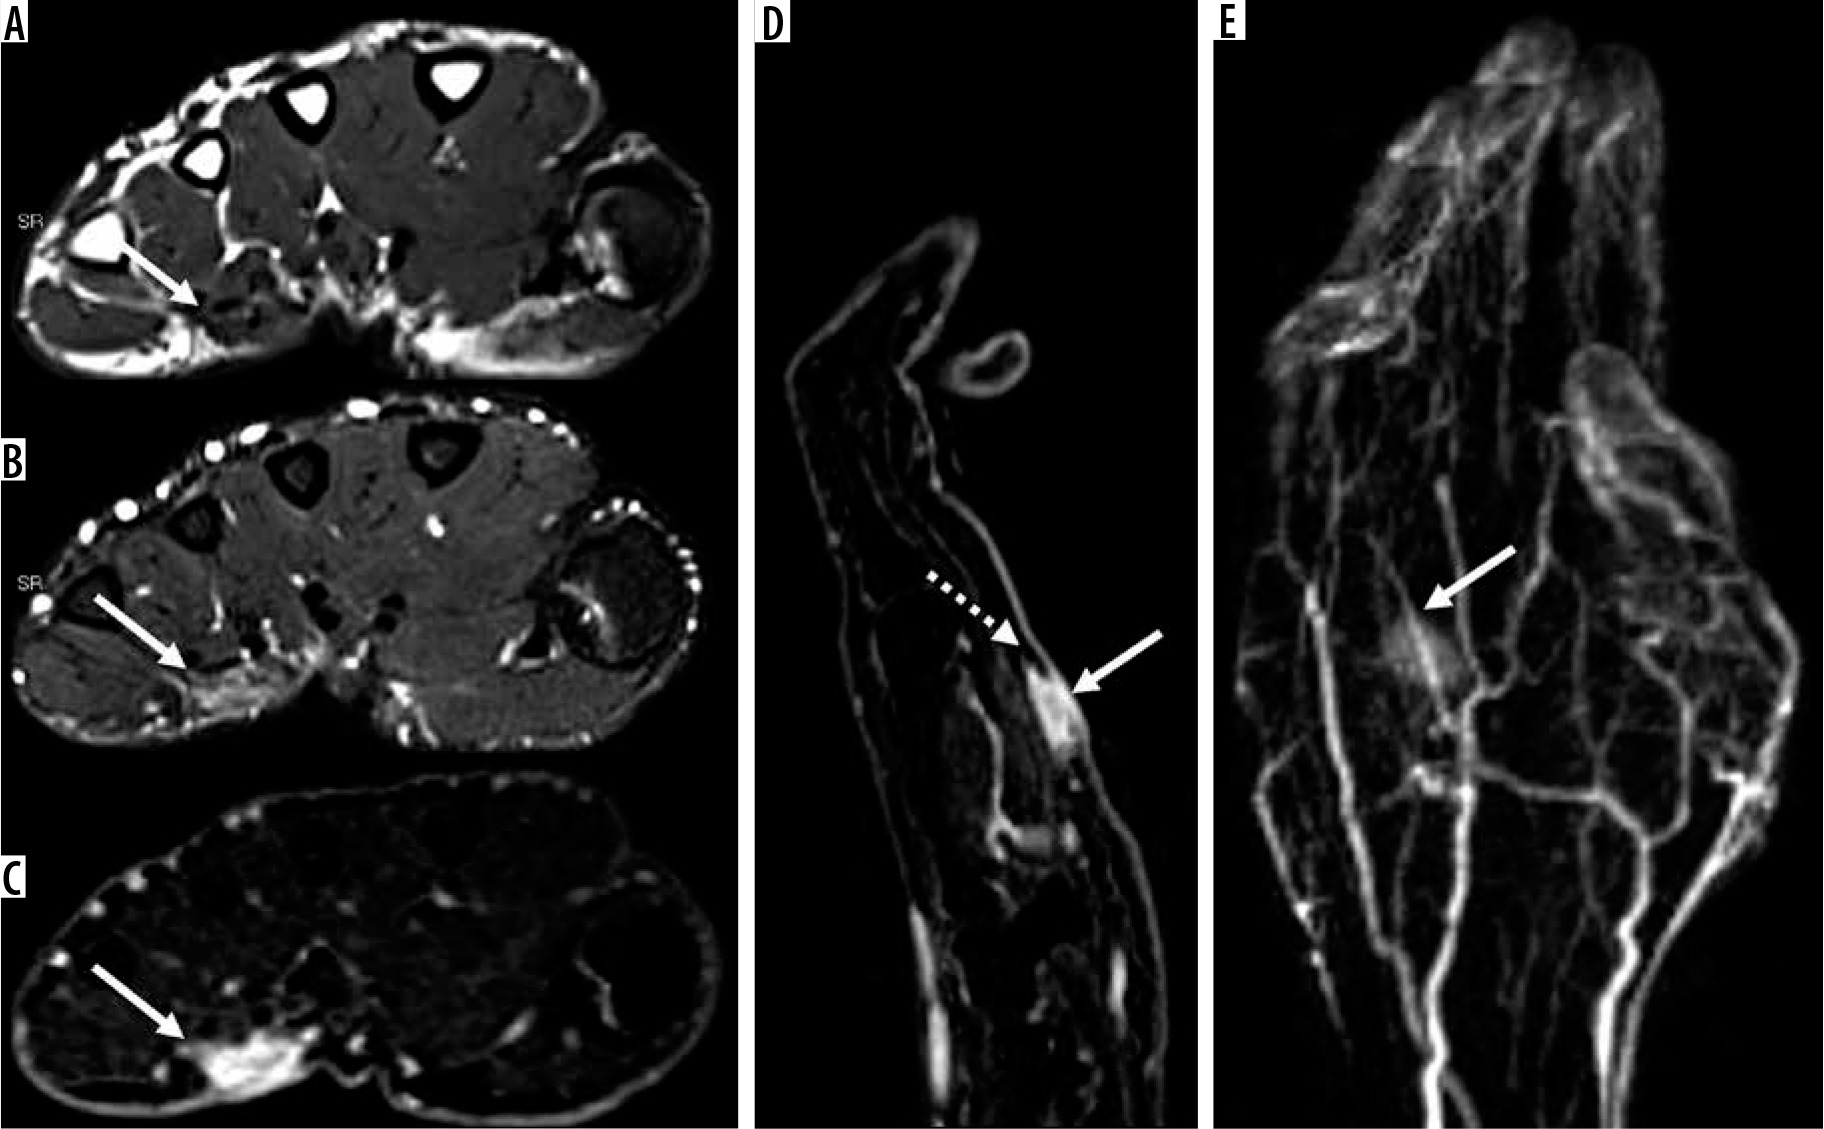

Figure 10

30-year-old woman with recurrent clear cell sarcoma. Axial T2-weighted magnetic resonance (MR) image (A) and ADC map (B) through the upper lumbar spine show a right paraspinal unencapsulated soft tissue mass (arrow) of heterogeneously low signal intensity. There is qualitative restricted diffusion on DWI using low b-value of 50 s/mm2 (C), intermediate b-value of 400 s/mm2 (D), and high b-value of 800 s/mm2 (E) with lack of signal loss on DWI with increasing b-values. On the axial ADC map (B), there is qualitative restricted diffusion or low signal and quantitatively low ADC values, compatible with malignancy. Sagittal STIR MR image (F) shows perilesional oedema and internal septations within the mass (arrow). There is early arterial enhancement on DCE MIP (G) and heterogeneous enhancement on axial T1-wighted fat-suppressed post-contrast axial MR image (H) (arrows). Features of malignancy include restrictive diffusion on DWI/ADC mapping and early arterial enhancement